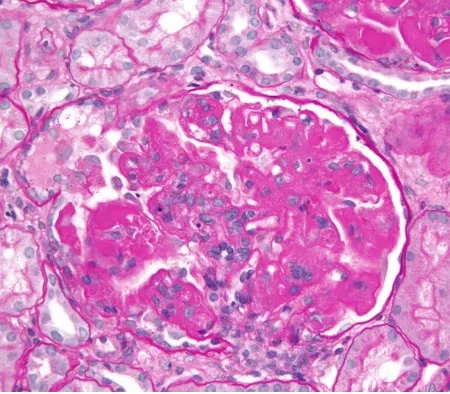

Injúria Renal Aguda (revisão Lancet 2025)

Injúria Renal Aguda (revisão Lancet 2025)